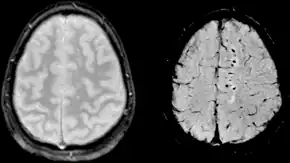

| Sårbarhedsvægtet bilede (SWI) af diffus axonal skade ved et traume med 1,5 teslaer (højre) | |

Diffuse axonal skade (DAI) er en hjerneskade hvor skader i form af ekstensive læsioner i hvid substans-tragter sker over et stort areal. DAI er en af de mest almindelig og ødelæggende typer af traumatisk hjerneskade,[1] og er en stor årsag til bevidstløshed og vedvarende vegetativ tilstand efter voldsomme hovedtraumer.[2] Det sker hos cirka halvdelen af alle voldsomme hovedtraumer og kan være den primære skade der sker ved hjernerystelse. Udfaldet er ofte koma, hvor mere end 90 % af alle patienter med voldsom DAI aldrig genvinder bevidsthed.[2] Dem der vågner op forbliver ofte signifikant svækket.[3]

DAI kan opstå i enhver sværhedsgrad fra meget mild eller moderat, til meget voldsom.[4] Hjernerystelse kan være en mildere type af diffus axonal skade.